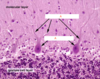

label A-C of (from the ear)

A: scala vestibuli

B: scala media

C: scale tympani